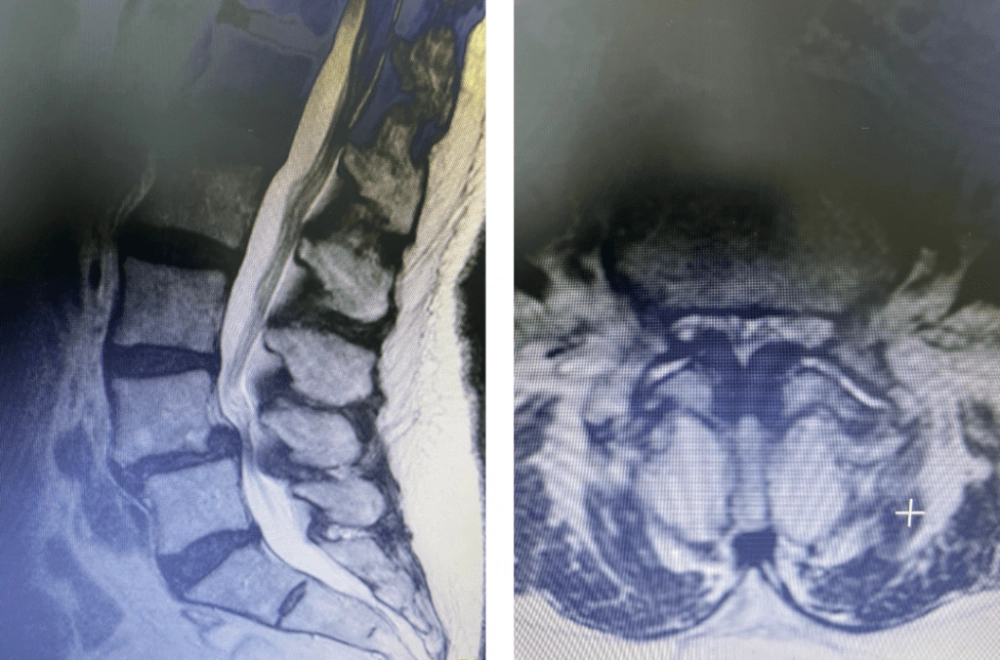

An overview of what is spinal stenosis